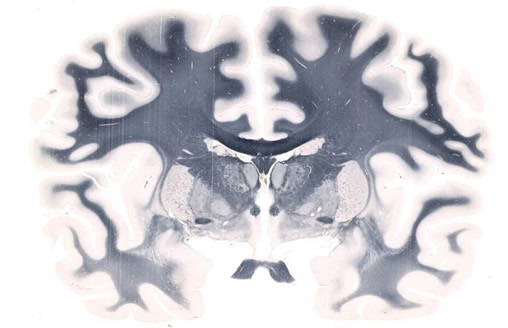

Whole-mount Brain scanned on a 5" x 7" slide at 20X resolution

Figure 1. Whole-mount Brain scanned on a 5" x 7" slide at 20X resolution. Image credit: Huron Digital Pathology.